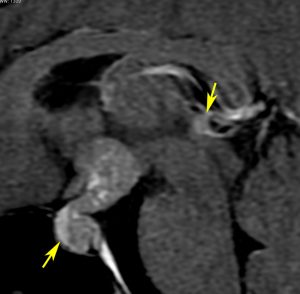

軽度の複視のみで発症した20代前半男性です。右上のように松果体腫瘍の前に割れ目が入るように第3脳室があり,両側視床に浸潤するために軽度の視床浮腫があり,ガドリニウムで強く増強され一部にのう胞があります。これだけでもgeriminomaにかなり特有の所見です。さらに,灰白隆起(矢印)のところに小さな神経下垂体germinoma腫瘍があります (bifocal tumor)。HCGは測定限界以下,AFP 2.5で,水頭症はありません。全ての臨床所見がgerminomaであることを示しています。

生検病理診断をしないでICE化学療法を1コース終えた後の画像です。腫瘍は消失しています。これでgerminomaであることが確認できたので,ICE化学療法を2コース追加して,25.2グレイの全脳室照射をして治療を終了しました。